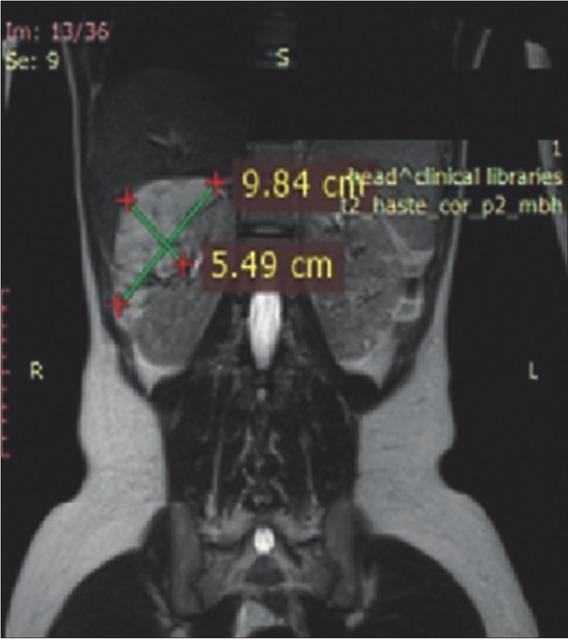

Figure 1